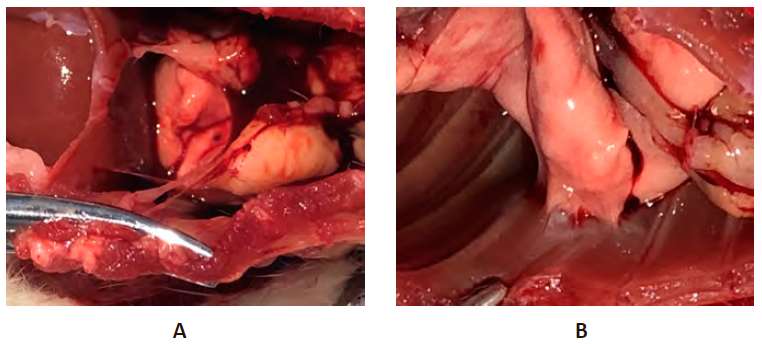

Рисунок 2 – Плевральная полость на 10-е сутки экспериментальной травмы грудной клетки

Примечание: А. Группа негативного контроля. Б. Опытная группа. Введение плазмы, обогащенной тромбоцитами (PRPт). Отсутствие консолидации реберных отломков.

Консолидация реберных отломков на 20-е сутки эксперимента зафиксирована у 66,7% животных группы НКт и у 77,8% – опытной группы. Спайки в группе НКт, как и на предыдущем сроке эксперимента, преимущественно образовывались в зоне операционной травмы – в 43,3% и были представлены паутинными и пленчатыми сращениями (рис. 3А).

При введении плазмы, обогащенной тромбоцитами (PRPт) на 20 сутки в плевральный полости лишь в 1 случае (3,3%) спайки отсутствовали, в остальных случаях было зафиксировано спайкообразование с тотальным заращением плевральной полости в 13,3% (4 случая). Наиболее часто определялись спайки в зоне перелома – 40,0%, а также единичные локальные спайки (20,0%) и единичные спайки вне зоны перелома (23,3%). Спаечные сращения были представлены плотными, плоскостными спайками (рис. 3Б).

Рисунок 3 – Плевральная полость на 20-е сутки экспериментальной травмы грудной клетки

Примечание: А. Группа негативного контроля. Наличие консолидации переломов ребер, отсутствие внутриплевральных спаек. Б. Опытная группа. Введение плазмы, обогащенной тромбоцитами (PRPт), образование плевральных сращений.

На 30-е сутки эксперимента в группе НКт отмечалась консолидация мест перелома с образованием выраженной костной мозоли. Отмечено сужение и деформация межреберных промежутков, сформировавшихся за счет спаечного процесса. Тотального заращения плевральной полости не выявлено (рис. 4А).

К окончанию эксперимента (30-е сут.) в группе PRPт тотальное заращение плевральной полости наблюдалось в 13,3% (4 случая). На рис. 4Б представлена наиболее типичная ситуация, характеризующаяся формированием плоскостной интимной спайки в месте перелома при биостимуляции адгезиогенеза плазмой, обогащенной тромбоцитами. Протяженность спайки – 10 мм, ширина 4 мм, толщина до 1 мм, общая площадь органной спайки составила 40 мм2, отмечалось оскуднение васкуляризации по сравнению с предыдущим сроком.

Рисунок 4 – Плевральная полость на 30-е сутки экспериментальной травмы грудной клетки

Примечание: А. Группа негативного контроля. Наличие консолидации переломов ребер, отсутствие внутриплевральных спаек. Б. Опытная группа. Введение плазмы, обогащенной тромбоцитами (PRPт). Формирование плоскостных спаек.